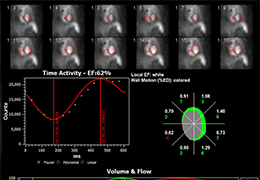

Performs 3D reconstruction and volume rendering.

Multi-planar slicing.

High-quality and fast 3D reconstruction and 3D rendering